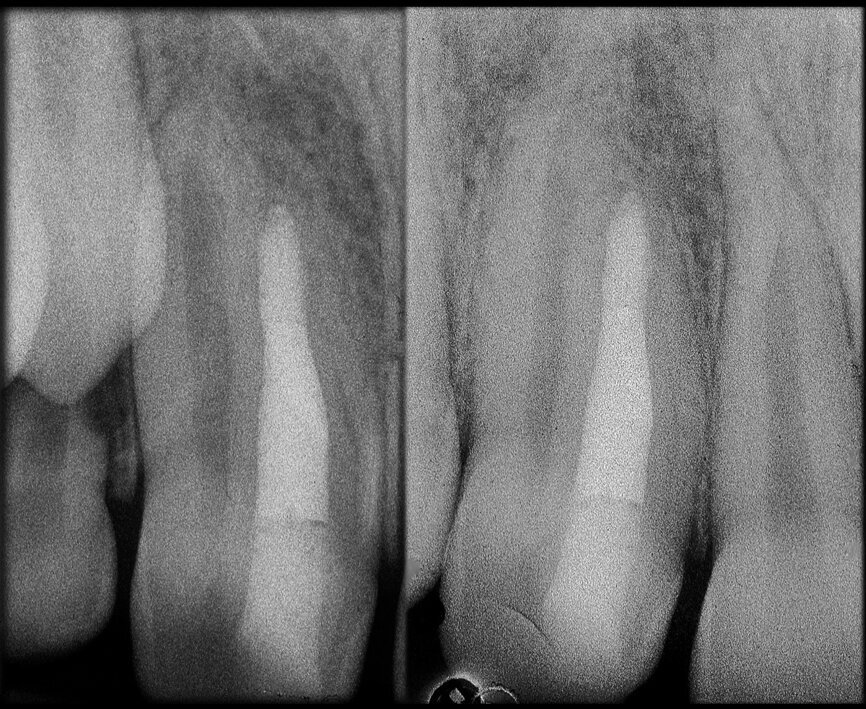

The case with which I would like to start my clinical review is a perfect example of how difficult it is to establish the origin of the patient’s symptoms on the basis of an intraoral radiograph alone. Not only does the 2D study fail to establish with certainty the presence of a lesion, but more importantly, it is impossible to establish the size, morphology and type of the lesion. An analysis of the 3D imaging, however, provides a clear picture of the clinical situation: the coronal and sagittal slices revealed the presence of a large lesion extending from the apex of the mesial root of this molar to the furcation, while the axial slices allow us to conduct a precise analysis of the endodontic anatomy and, in particular, the shape of the mesial root, which in this case was fused with the palatine root. A full overview of the case can, therefore, guide the decision-making process and direct the treatment plan towards a specific type of treatment (Figs. 1–4).